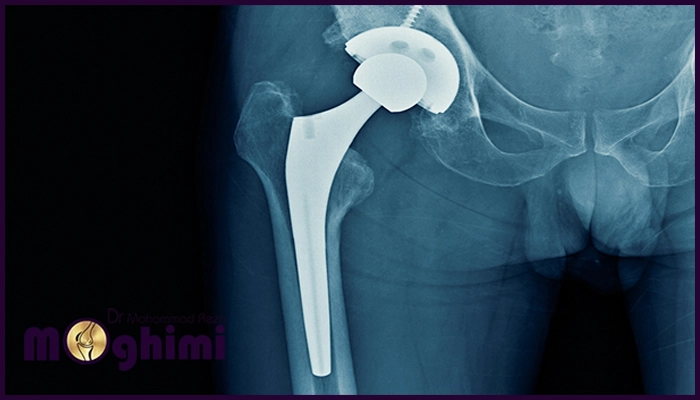

انتخاب بهترین جراح تعویض مفصل لگن نقش حیاتی در بازگرداندن تحرک و کاهش درد بیماران مبتلا به آرتروز یا آسیبهای شدید لگن دارد در واقع یک جراح متخصص و باتجربه، کیفیت نتایج جراحی و سرعت بهبود را بهطور چشمگیری افزایش میدهد. دکتر محمدرضا مقیمی با تجربه گسترده در جراحی تعویض مفصل لگن، مهارت بالا و توجه به جزئیات، توانسته نتایج موفقی در بهبود کیفیت زندگی بیماران ارائه کند و مسیر درمان ایمن و مطمئنی فراهم کند.

جراحی تعویض مفصل لگن زمانی ضرورت پیدا میکند که آسیب یا بیماری مفصل لگن باعث درد شدید، کاهش تحرک و اختلال در فعالیتهای روزمره شود، این جراحی با هدف بهبود کیفیت زندگی، کاهش درد و بازگرداندن عملکرد طبیعی مفصل انجام میشود از جمله مهمترین دلایل انجام این عمل عبارتند از:

دکتر محمدرضا مقیمی بهعنوان یکی از برجستهترین جراحان تعویض مفصل لگن در تهران شناخته میشود، تجربه گسترده و مهارت بالای ایشان در جراحیهای پیچیده لگن، نتایج موفقیتآمیز و رضایت بیماران را به همراه داشته است. دکتر مقیمی با استفاده از تکنیکهای نوین و کمتهاجمی، درد را کاهش داده و تحرک طبیعی مفصل را بازمیگرداند. توجه دقیق به جزئیات و برنامهریزی شخصی برای هر بیمار، از ویژگیهای متمایز ایشان است توجه داشته باشید که انتخاب ایشان، مسیر درمانی امن و مطمئن برای بازگرداندن کیفیت زندگی بیماران فراهم میکند.